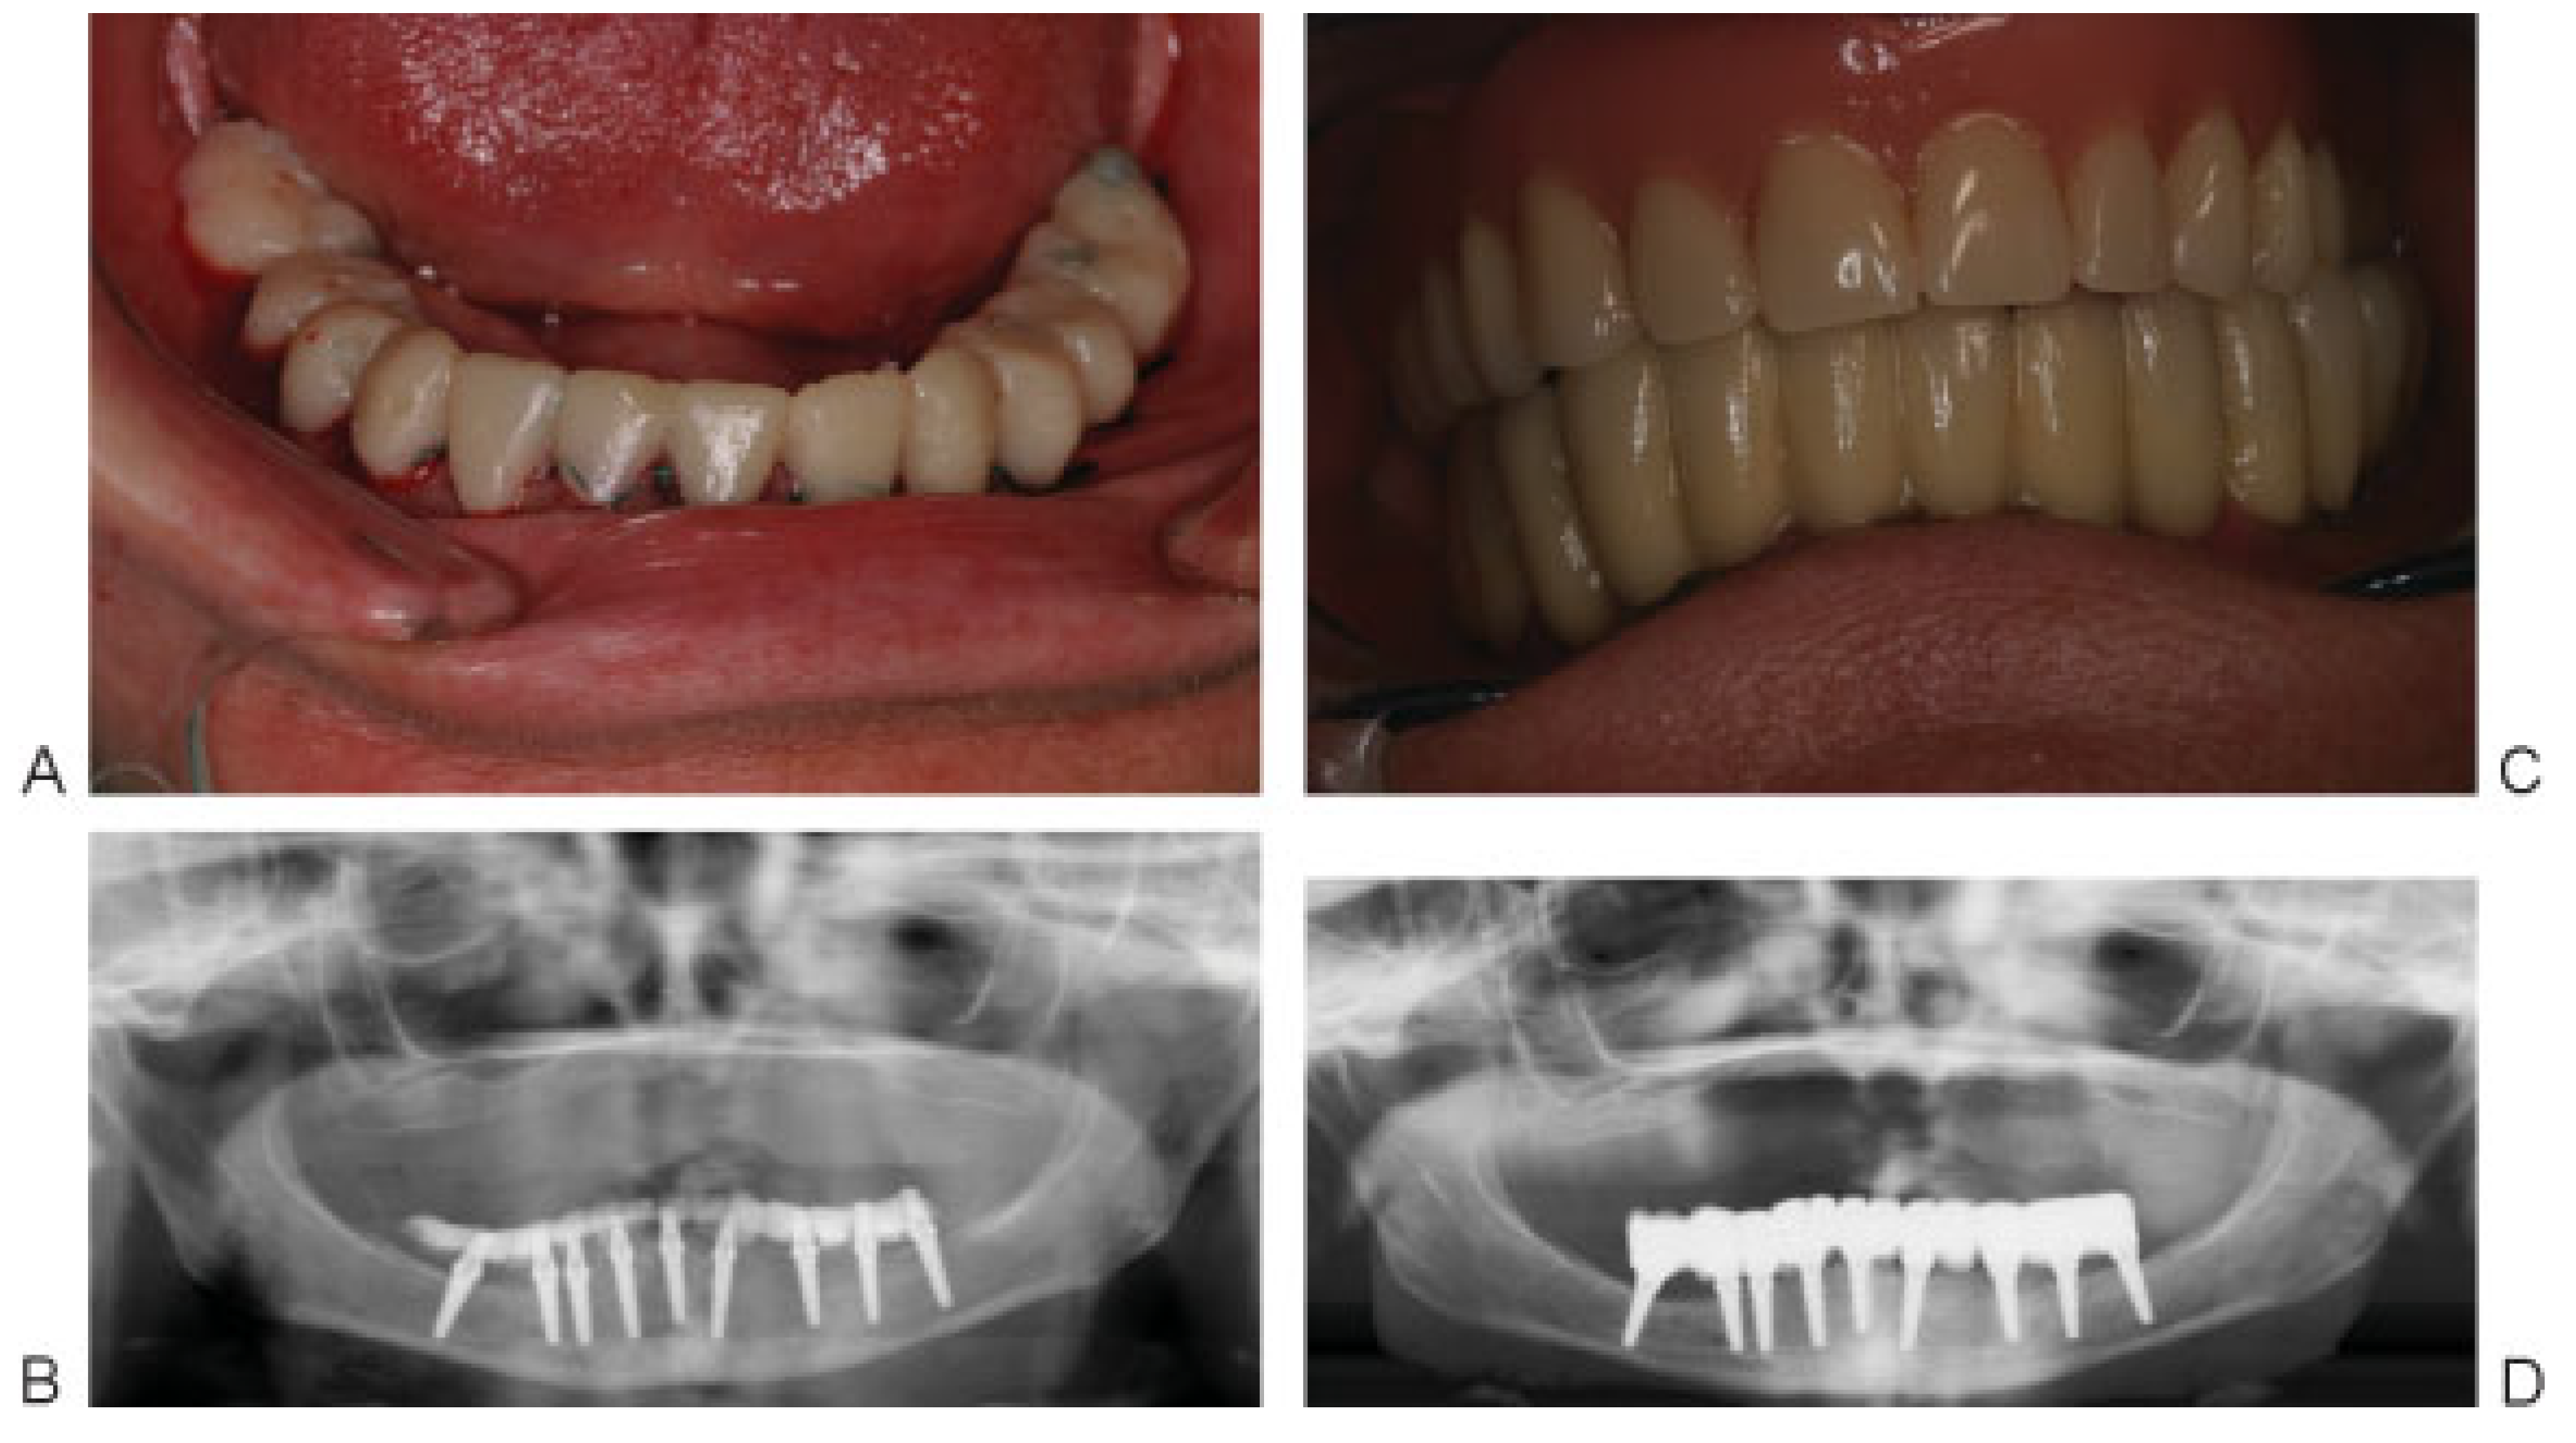

Figure 5. (A) Atraumatic extraction of the six anterior teeth followed by curettage of the sockets and removing any bony spicules using bone rongeur. (B) Drilling 3 mm in the depth of the lingual wall using pilot drill followed by threaded bone expander no. 2 to allow for bone condensation against the walls of the osteotomy, which aids in better implant stability and positioning the implant buccally without compromising esthetics. (C) MRT implant in place. (D) Continue the same procedure in other sockets. (E) Four postextraction MRT implants and positioning back the flap.

Bilateral IAN block anesthesia was then given to the patient and atraumatic simultaneous extraction of the anterior teeth was performed. Four 3.85-mm width MRT postextraction implants were inserted (two implants of 12-mm length and two implants of 14-mm length) (Figure 5).